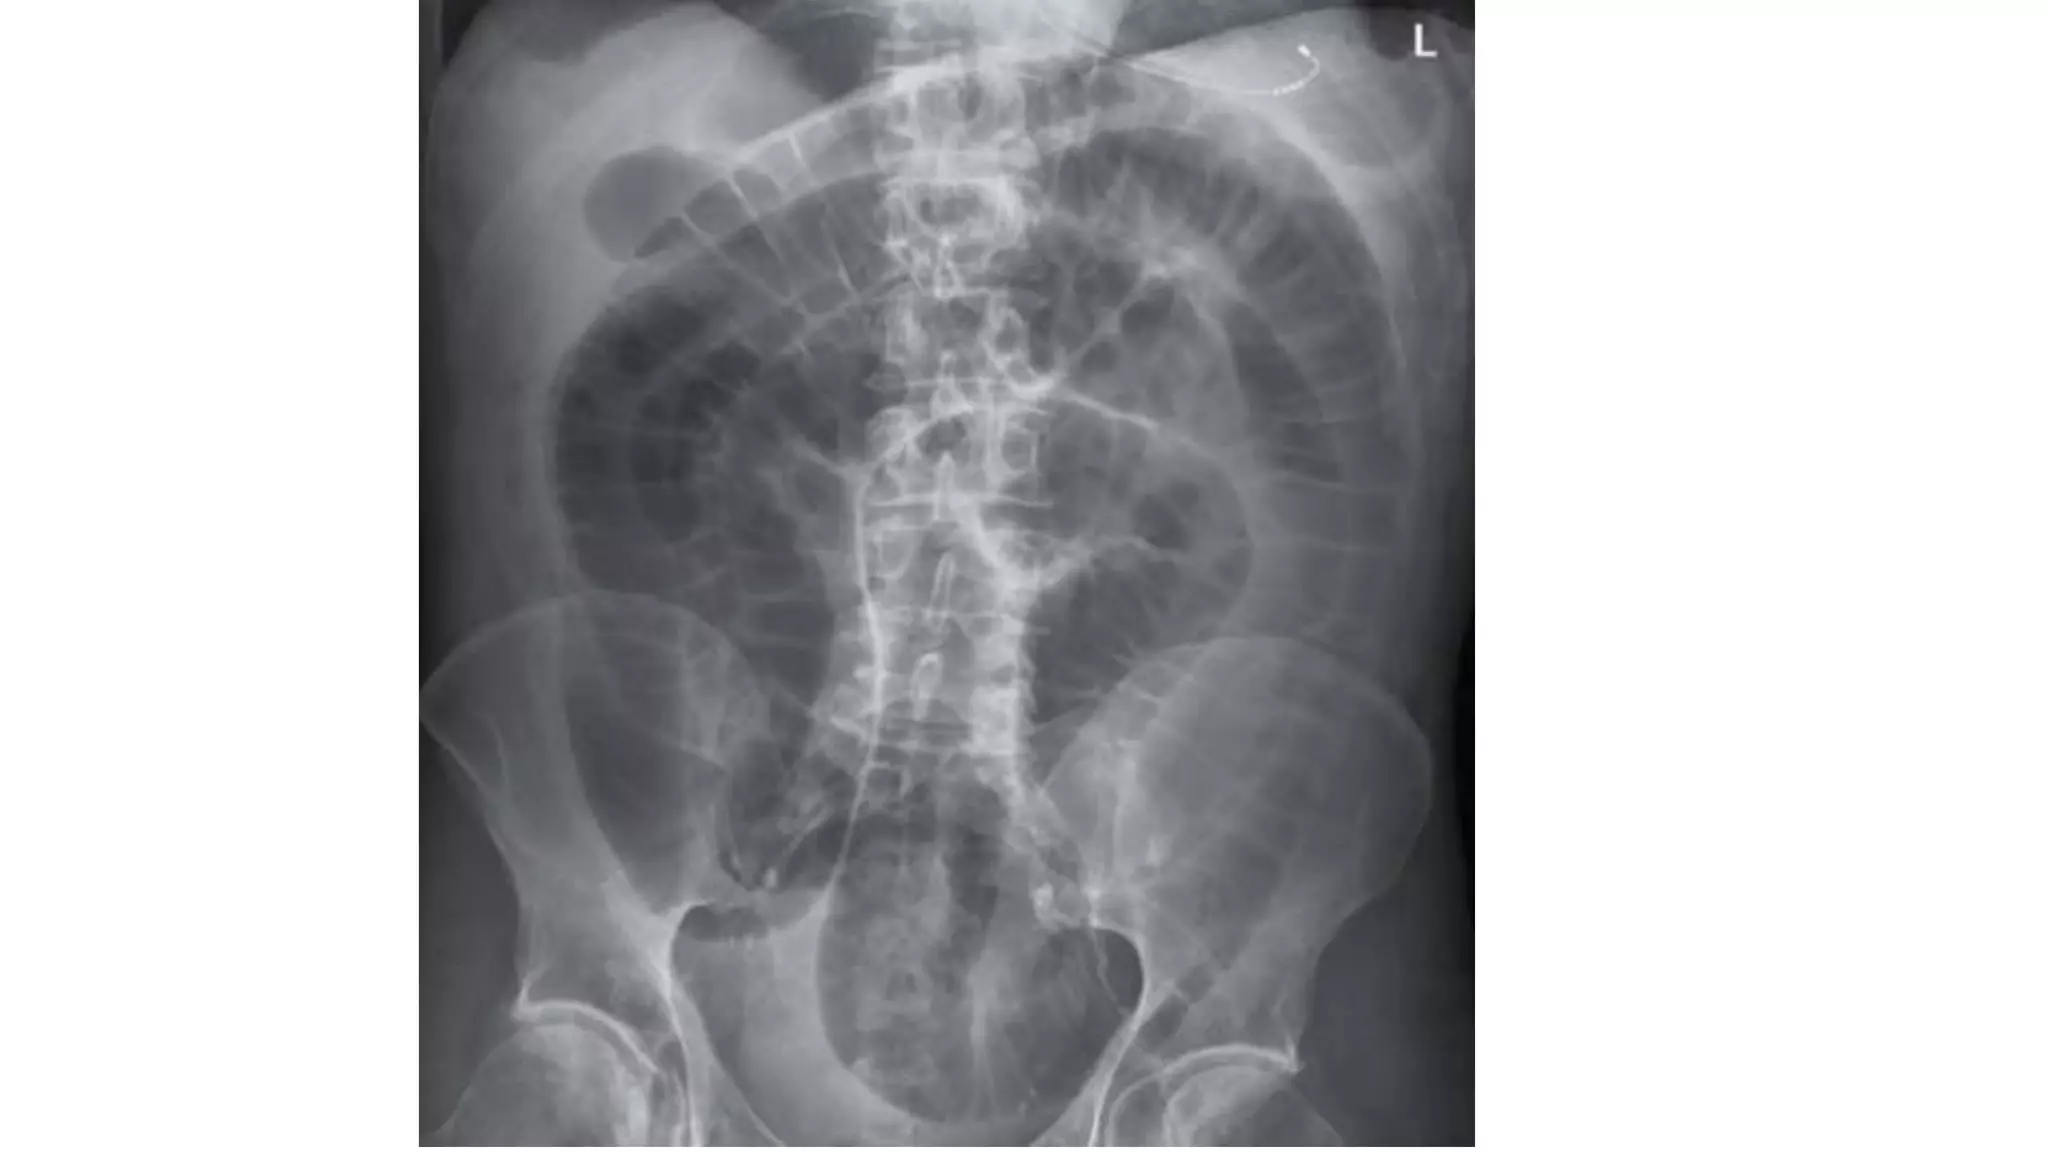

Radiological features in large bowel obstruction

• Colonic distension usually visualized in the periphery

• show the hustrations of the Taenia Coli.

• absence of rectal air and air fluid level if ileocecal valve incompetent

• May also demonstrate the cause of obstruction (volvulus)

Radiological signs to look for:

• Dilation >3 cm: The small bowel is dilated if it measures over 3 cm in

diameter.

• Central location: The dilated loops are more likely to be centrally

located on the abdominal radiograph.

• Valvulae conniventes: These are the mucosal folds of the small

intestine. They are thin, closely spaced and classically seen as a

continuous thin line across the entire width of the bowel.

• Air fluid level in upright position